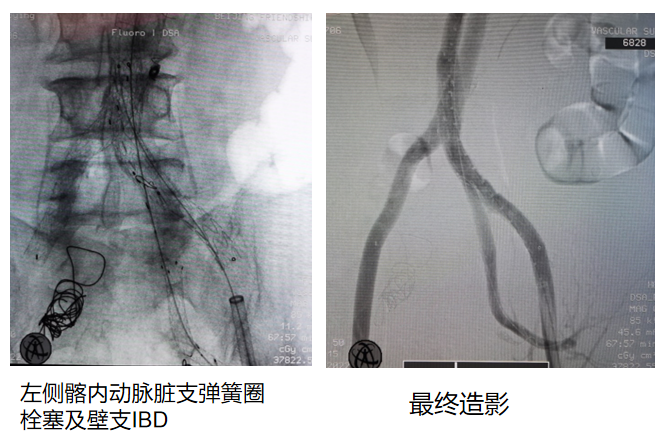

手术过程

术中通过血管造影精准定位左侧髂内动脉动脉瘤位置,采用弹簧圈对左侧髂内动脉进行栓塞,同时释放支架于髂内动脉分支(IBO),以重建髂内动脉血运并隔绝动脉瘤。最终造影显示操作部位血流分布改善,动脉瘤区域血流阻断,支架位置合适。

术后随访

术后7天CTA显示支架位于髂内动脉分支内,血流通畅,无内漏等并发症迹象,周围组织未见异常。术后7月CTA检查,支架持续保持良好位置,髂内动脉分支血运稳定,动脉瘤无复发及增大,血管周围组织状态正常,表明手术远期效果良好。